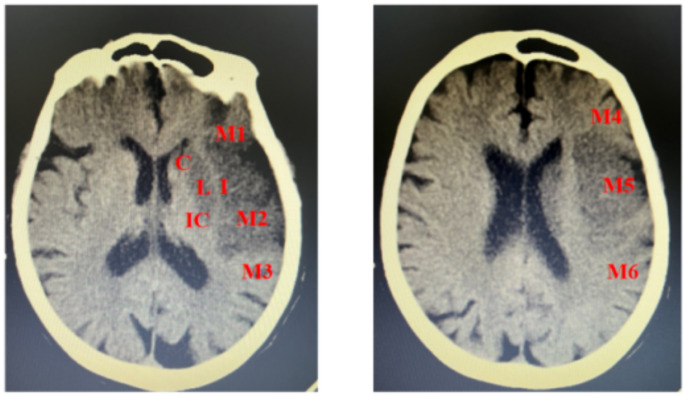

Background: Large hemispheric infarction (LHI) of the middle cerebral artery (MCA) is linked to high mortality and morbidity. This study aims to investigate the characteristics of large artery atherosclerosis (LAA) and cardioembolism subtypes of LHI in MCA.

Methods: This retrospective cohort study included 70 patients with LHI hospitalized at the Second Affiliated Hospital of Anhui Medical University from May 2019 to May 2021. Patients were classified according to the TOAST classification into LAA and cardioembolism subtypes.